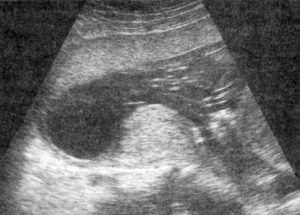

Одним из наиболее достоверных методов диагностики изменений тонуса миометрия является УЗИ. Повышение тонуса матки определяется в виде тотального или локального напряжения миометрия.

Но самый точный и распорстраненный способ — ультразвуковое обследование (УЗИ). Сканирование определит степень развития патологии. Есть специальные препараты, миометры или тонусометры. Такое оборудование используется редко при более сложных случаях, потому что патологию легко выявить другими методами.

В качестве основного метода определения гипертонуса врачи проводят ультразвуковое исследование. Такая процедура помогает визуально определить тотальное или локальное сокращение мышцы детородного органа.

Как правило, наблюдается уплотнение поверхности матки с определенной стороны. Если выявляется данный признак в области прикрепления плаценты, существует вероятность ее отслоения. Также может наблюдаться утолщение всего миометрия, что подтверждают возникающие клинические симптомы.

Определить локальный гипертонус матки по задней или передней стенке можно с помощью ультразвукового исследования. При этом на УЗИ видно изменение стенки матки в месте её тонуса, она прогибается вовнутрь.

информацияВ последнем случае нарушение может быть не всегда выявлено вовремя, так как внешние характерные симптомы иногда отсутствуют, поэтому в некоторых случаях обнаружить избыточное напряжение маточных мышц можно только с помощью ультразвукового исследования (УЗИ).

Наиболее распространенным методом диагностики при подозрении на развитие гипертонуса задней стенки матки является УЗИ. С помощью указанной процедуры врач получает возможность оценить состояние маточных стенок, определить их толщину и возможное напряжение мышечного слоя.

Во время проведения УЗИ специалист также определяет состояние шейки матки с целью возможного обнаружения признаков ее укорочения или раскрытия зева.